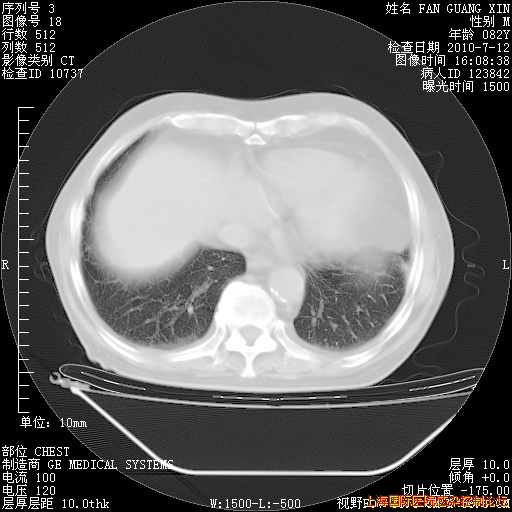

补发6月12日肺部CT肺窗

6月12日肺窗